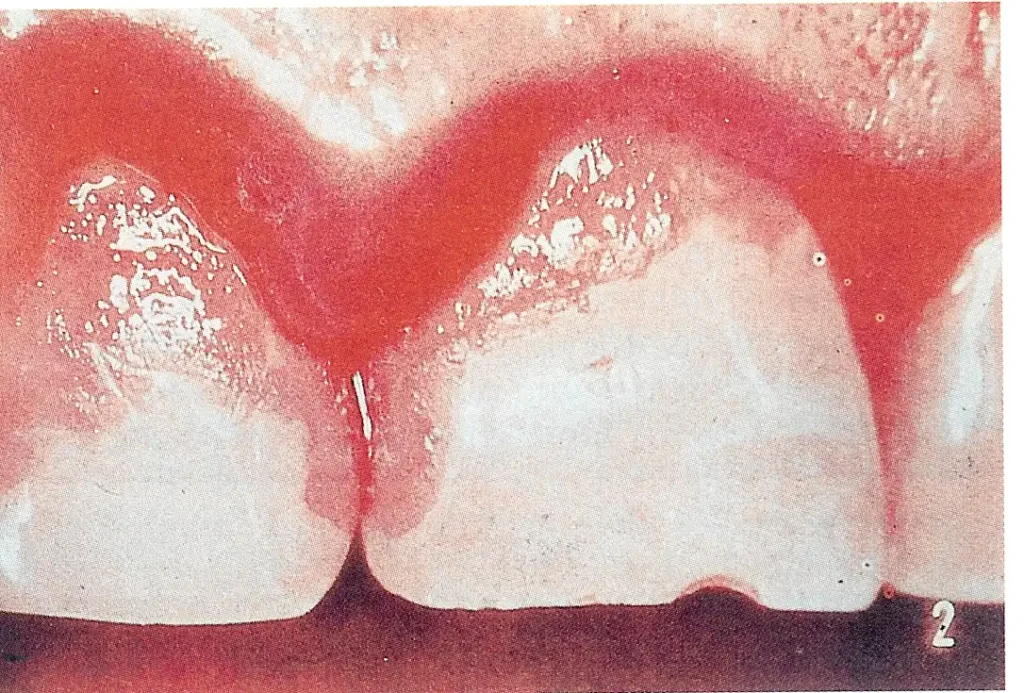

A fogak fő ellensége a cukor! A fogszuvasodás kialakulása szempontjából nem elsősorban az elfogyasztott mennyiség, hanem a cukorbevitel (szénhidrát) gyakorisága a döntő, mivel ilyenkor többszöri savas hatás éri a fogzománcot. Ne legyen a gyermek keze ügyében édesített teával, szörppel, gyümölcslével teli innivaló, a szomjat oltsuk vízzel! A cukros oldattal gyakran érintkező fogak ugyanis igen gyorsan romlanak, letöredeznek. (kép: caries, caries3, szovodmeny)